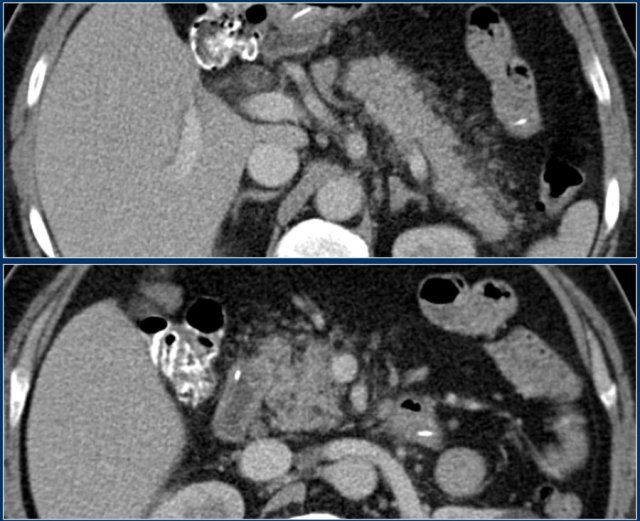

ANC (2)

Study the images and then continue reading.

What are the findings?

The findings are:

- Normal enhancement of the entire pancreas.

- Extensive peripancreatic collections, which have liquid and non-liquid densities on CT.

- There are at least two collections, but no pancreatic parenchymal necrosis (CTSI: 4).

- On day 18 there is expansion of the peripancreatic collections and an incomplete wall is present.

On day 5 this collection can be diagnosed as probable acute necrotic collection.

On day 18 an incomplete wall is present, but we can assume that in a couple of days this will be a walled-of-necrosis with a complete wall.

When peripancreatic collections persist or increase, it is usually due to the presence of fat necrosis.

Because fat does not enhance on CT, the diagnosis of fat necrosis can be difficult.

Necrosis can be diagnosed with MRI, which of course should only be performed if it has direct clinical implications.